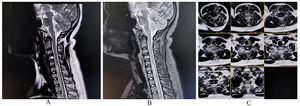

A complete metabolic panel was within normal limits. MRI of the spinal cord revealed a longitudinally extensive spinal cord lesion over the dorsal cord extending from D4 to D10 (Fig. 4A, B, C). Nerve conduction studies study after 1 week revealed an acquired axonal sensorimotor polyneuropathy. Metabolic, nutritional, inflammatory, infective, and immune-mediated etiologies were ruled out precisely with relevant investigations. Amid toxic myeloneuropathies, other causes were ruled out precisely from historical correlates, and a diagnosis of heroin-induced myeloneuropathy was performed. His recovery was incomplete despite pulse intravenous methylprednisolone therapy followed by intravenous immunoglobulin infusion.